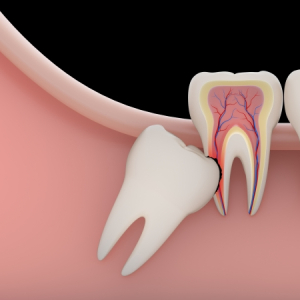

Khi nào cần nhổ răng khôn? Dấu hiệu răng khôn mọc lệch, mọc ngầm

Răng khôn mọc lệch: Dấu hiệu, nguyên nhân, cách xử lý